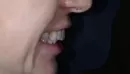

У меня были установлены брекеты на обе челюсти 10 лет назад. ИТОГ: переднею челюсть выдвинули вперед, образовались тремы, которые закрыли пломбами. Зубы верхней челюсти с наклоном вперед, нижнюю челюсть не дотянули, и передние зубы наклонили вперед (веером) до контакта с верхней.

Решила поставить брекеты повторно. Только на нижнюю челюсть. План лечения : 1. Передние зубы верхней с кистами и хрупкие, врач сказал нельзя давать нагрузку, предложил скорректировать внешний вид коронками. 2. Передние зубы нижней челюсти утопить на 1-2 мм и задвинуть назад (к языку) 3. Наклон передних четырех зубов верхней челюсти скорректировать коронками.

В результате повторного ношения брекетов наклоны изменили все зубы нижней челюсти. Пропало верное соотношение жевательных зубов ( верх - низ шестерок, 5,4,3), они друг на друге. Врач говорит, что это неважно, важнее соотношение клыков при ведении в бок и передних зубов при смыкании.

Также между клыками нет контакта. Врач предлагает ставить ретейнеры только на 4-ре зуба, чтоб остальные вернулись немного в прежнее положение и сами достигли контакта. Есть асимметрия челюстей по отношению друг другу или к черепу. Средняя линия верхней челюсти смещена немного относительно центра лица, а нижняя челюсть немного смещена относительно верхней челюсти. Ортодонт говорит, что он ровняет зубы, а не кости. Из анализов делали только панорамный снимок и фото зубов. То есть причину не изучали.